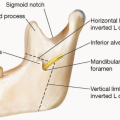

The external shape of the skull is composed of six bones— the frontal, parietal (two bones), temporal (two bones), and occipital.

The only soft tissues of relevance to the external skull shape are the temporal muscles on the side of the head.

The front to back shape of the skull is a convexity, whereas the sides of the skull are more linear or slightly concave.

The thickness of the skull and its three layers (two cortices and diploid space) vary widely at different positions of the skull as well as among different genders and ethnicities.